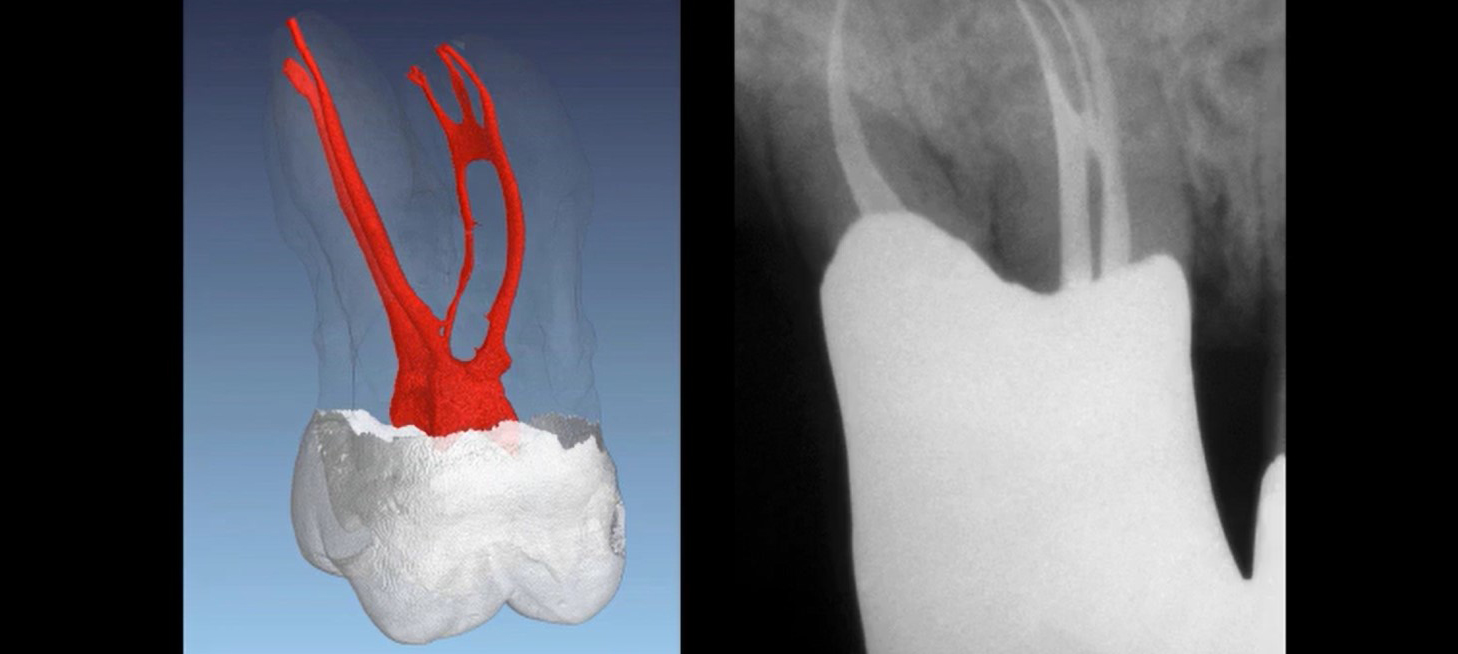

Endodontic Canal Preparation: Reciprocation

Endodontic Canal Preparation: Rotary